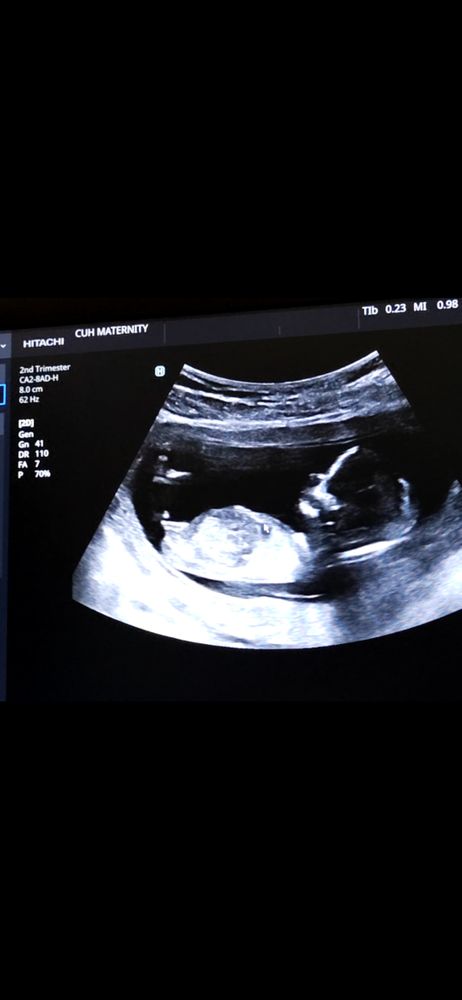

подскажите кого видите, на 13 неделе говорили ничего не торчит ,а на 17 на те,типо мальчик ,что скажите??

на этом сроке и у мальчиков и у девочек такой вот отросточек. Надо сбоку смотреть по его наклон. ВОт есть такая картинка, как отличить

У нас мальчик, на 12ти неделях было вот так

Недавно только читала как врачи определяют пол на таких сроках, мол, если торчит на 90° - то скорее всего мальчик, а если на 45° вниз то скорее всего девочка))